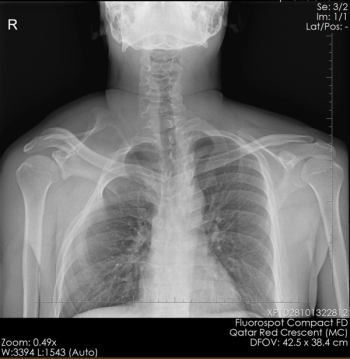

What is your diagnosis in this patient who presents for evaluation of scoliosis?